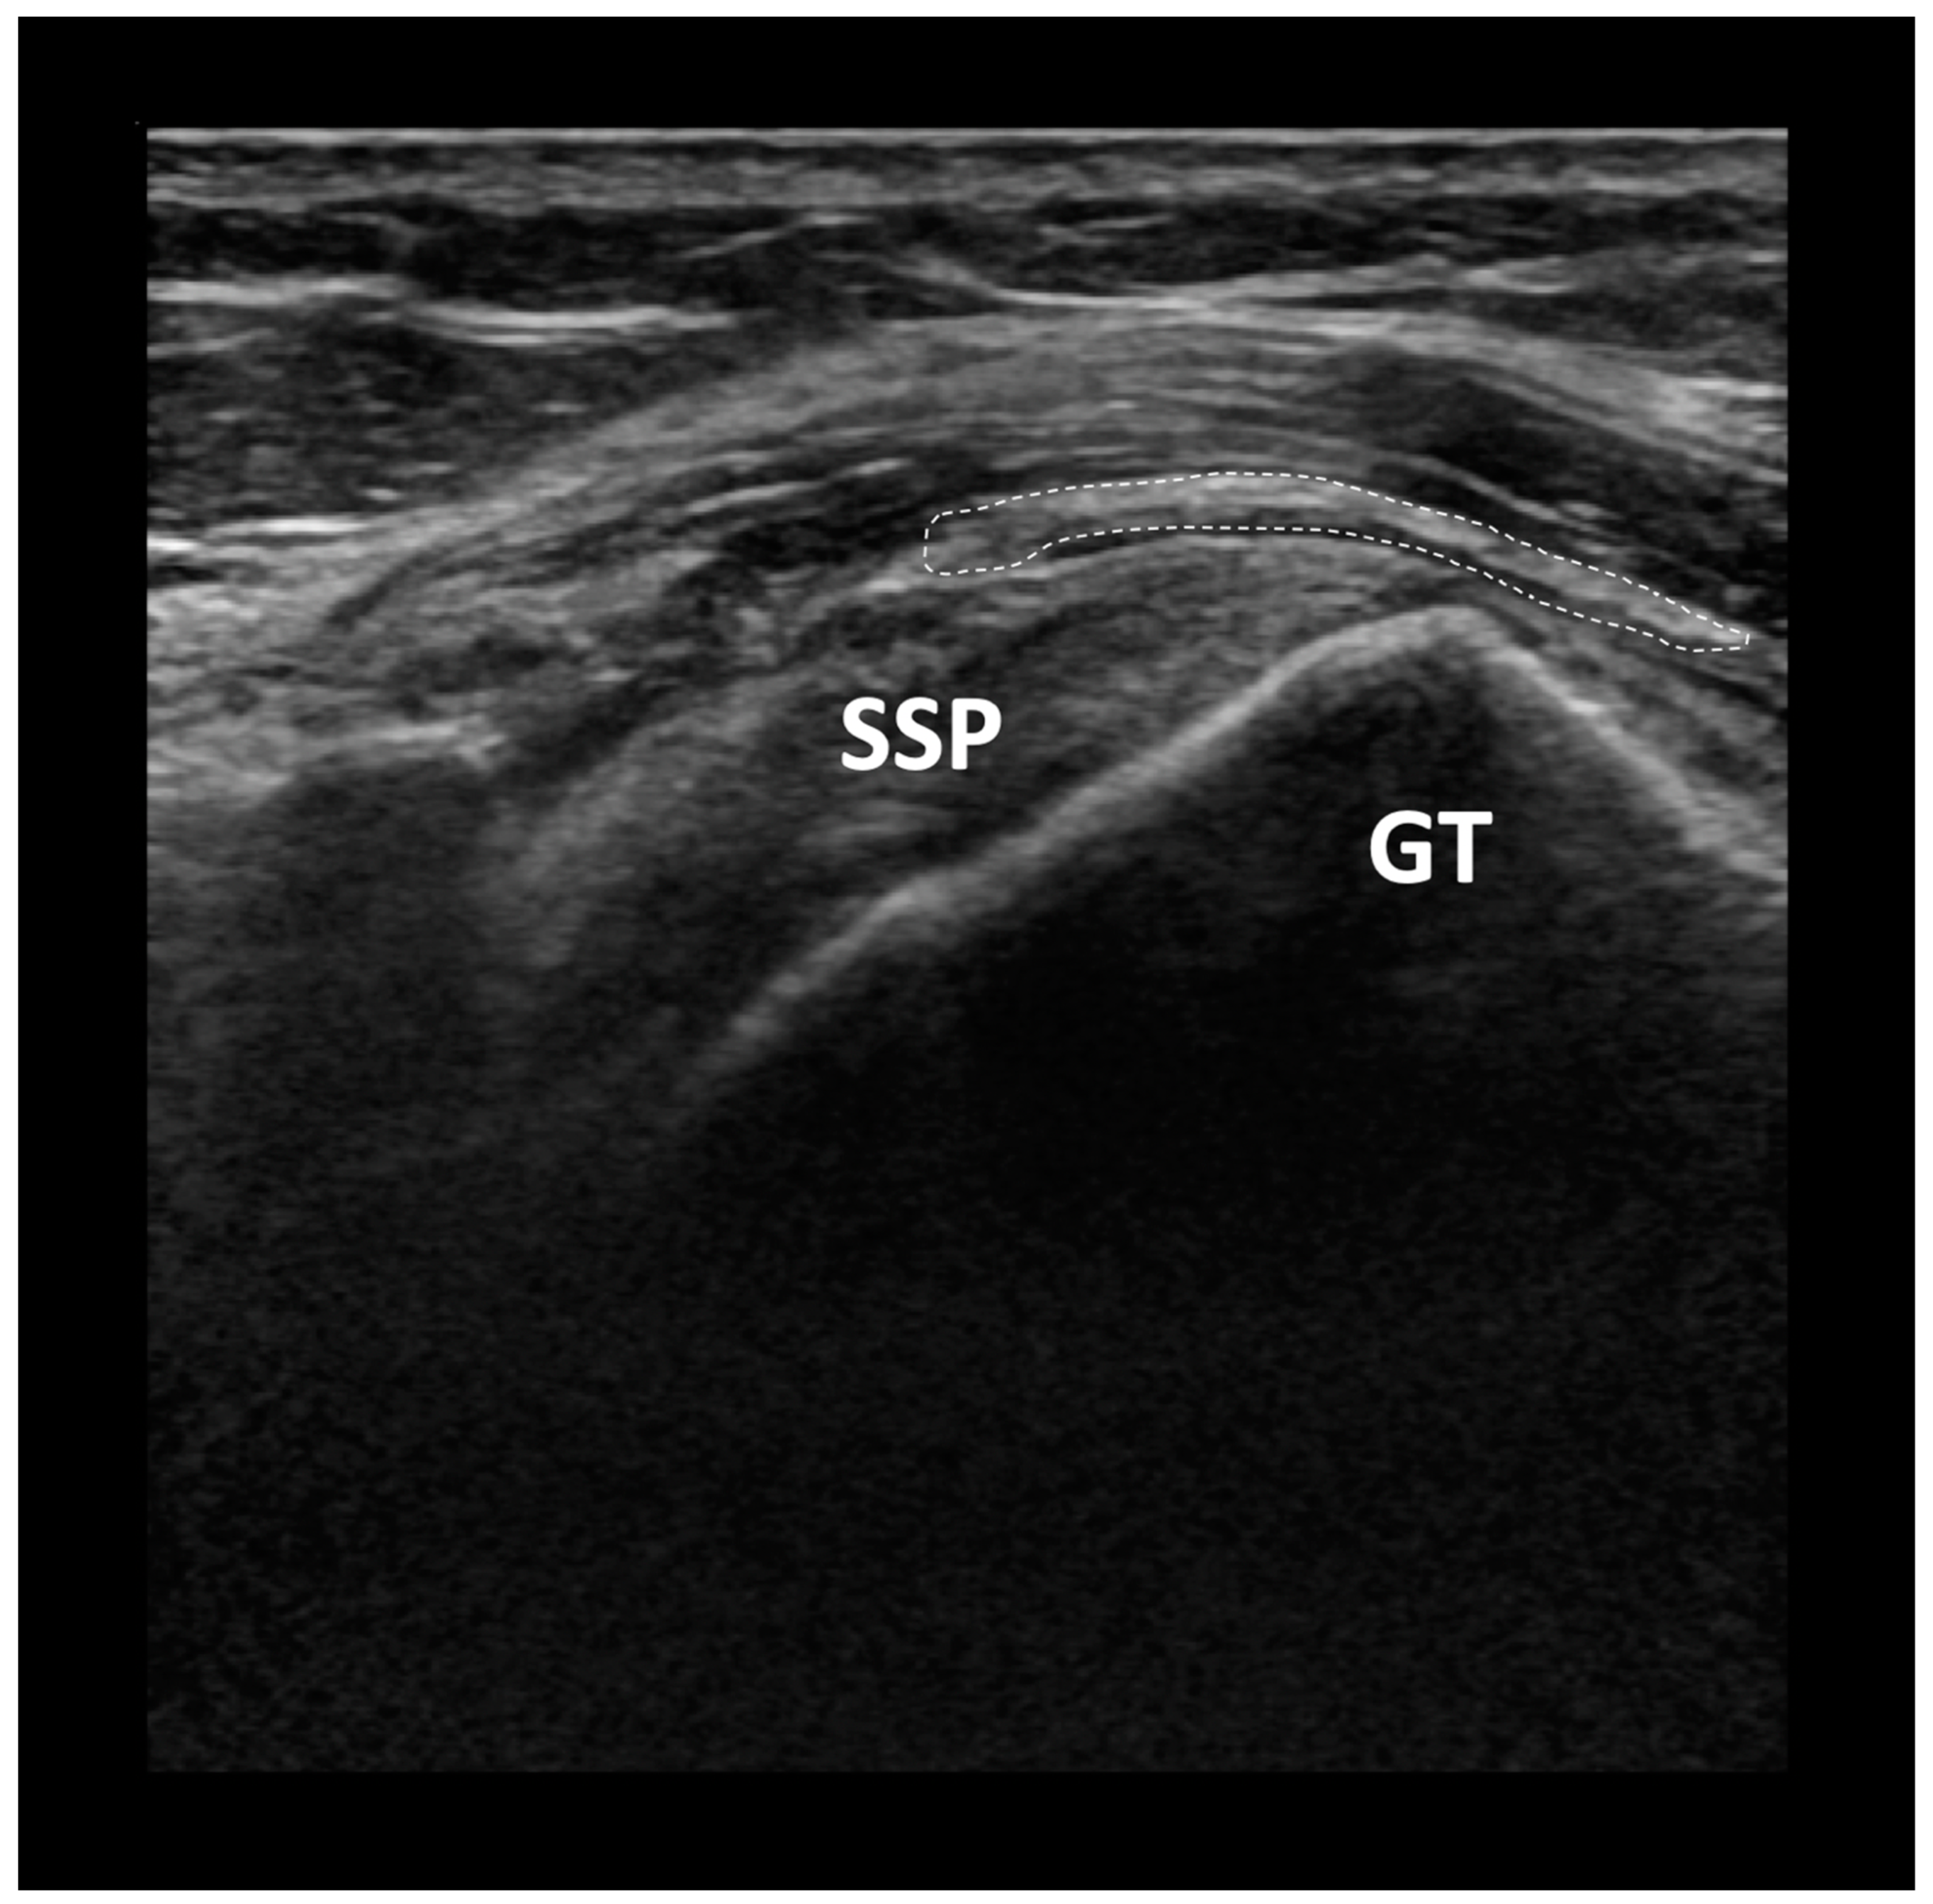

- Bokor, D.J.; Sonnabend, D.; Deady, L.; Cass, B.; Young, A.; Van Kampen, C.; Arnoczky, S. Evidence of healing of partial-thickness rotator cuff tears following arthroscopic augmentation with a collagen implant: A 2-year MRI follow-up. Muscles Ligaments Tendons J. 2016, 6, 16–25. [Google Scholar] [CrossRef]

- Schlegel, T.F.; Abrams, J.S.; Bushnell, B.D.; Brock, J.L.; Ho, C.P. Radiologic and clinical evaluation of a bioabsorbable collagen implant to treat partial-thickness tears: A prospective multicenter study. J. Shoulder Elb. Surg. 2018, 27, 242–251. [Google Scholar] [CrossRef]